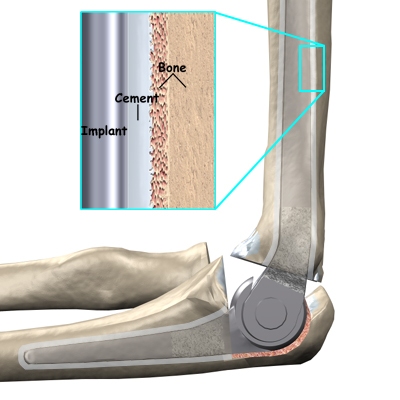

There are two different ways to hold the artificial elbow in place. A uses a special type of epoxy cement to glue it to the bone. The has a fine mesh of holes on the surface. Over time, the bone grows into the mesh, anchoring the prosthesis to the bone.